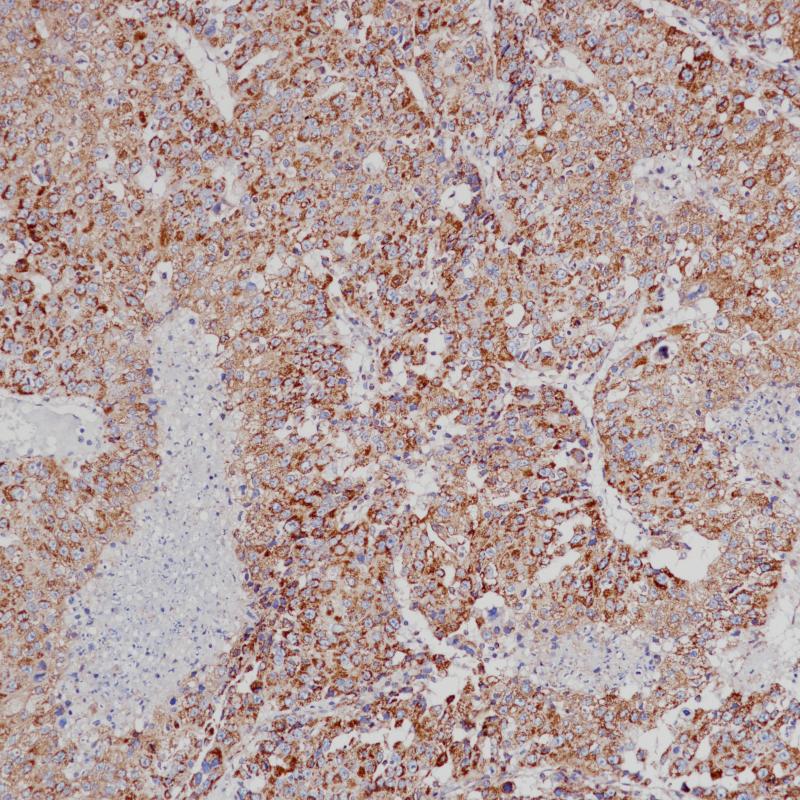

脊索瘤Brachyury(BP6218)染色

Brachyury蛋白由T基因编码,是一种转录因子,在脊椎动物胚胎发生过程中对后中胚层的形成和轴向发育至关重要。人类短肢在脊索以及沿脊柱发生的脊索瘤中表达,使其成为脊索和脊索衍生肿瘤的良好标记。人类T基因的一种常见多态性也被证明与多因素神经管缺损、脊柱裂的发展有关。

阳性对照

脊索瘤

亚细胞定位

细胞核